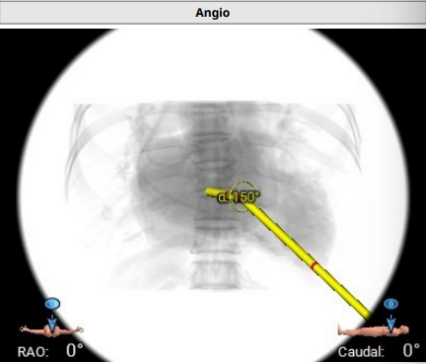

2.AV-MV double S curve :RAO 61°/ CAU 50°.此角度为二尖瓣主动脉瓣最佳观察位;

3.左心室和二尖瓣轴线角度:145°;

4.主动脉-二尖瓣角度:113°;

5.术中最佳投射角度:RAO 57° / CAU 14°;